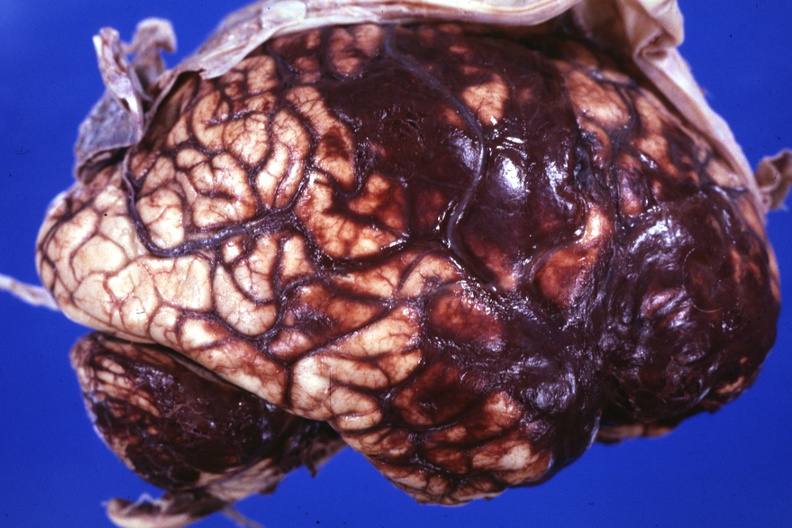

GROSS: NERVOUS: Brain: Hemorrhage: Subarachnoid recent large mycotic aneurysm ruptured 58 yom mitral valve repaired 11 years before death extensive pulmonary infection